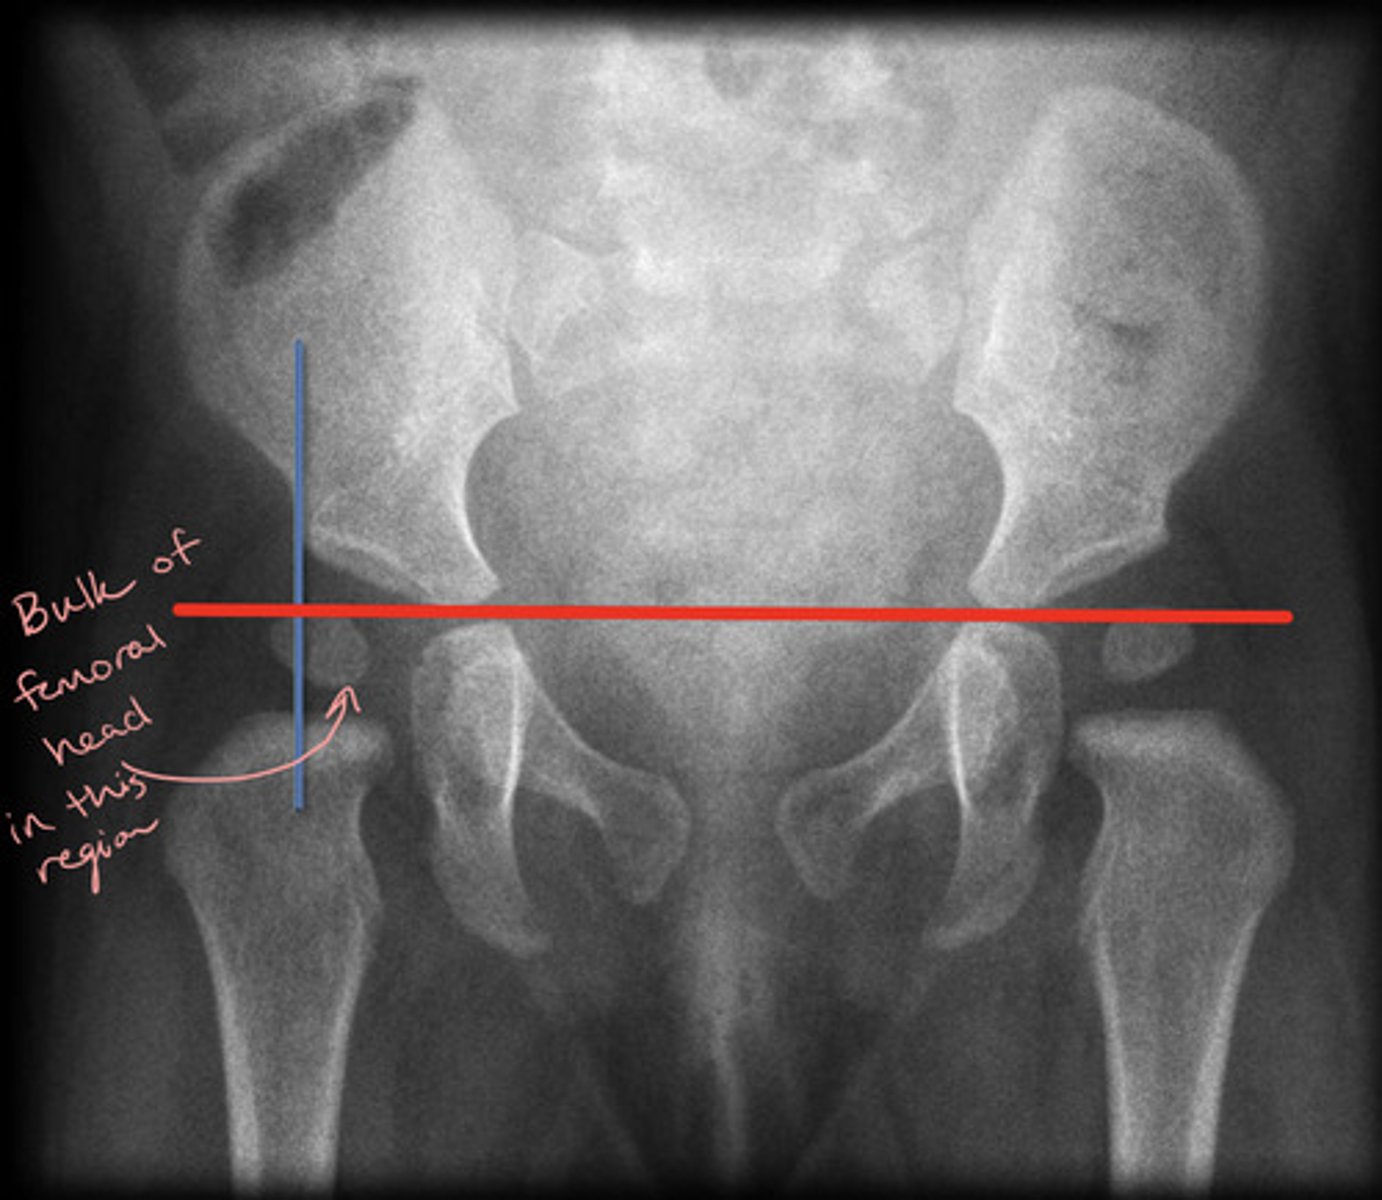

Perkin's Line

Line drawn vertically through the lateral most aspect of the acetabular roof perpendicular to Hilgenreiner's line

The ossified femoral head should be located in the inferomedial quadrant created

Acetabular Angle

Angle measured between Hilgenreiner's line and a line parallel to the acetabular roof

What is the normal bony coverage of the femoral epiphysis by the acetabular roof?

Greater than or equal to 50% coverage